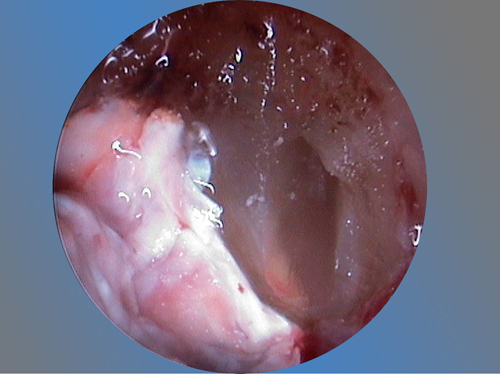

Es una intervención técnicamente exigente, que requiere formación e instrumentos especializados (microscopio, endoscopio, etc.), pero que correctamente realizada no causa molestias prácticamente y tiene unos resultados exitosos en más del 90% de los casos.